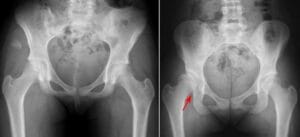

- X-rays: X-rays provide images of bones and help the doctor assess the alignment between the acetabulum and femoral head. They can also reveal signs of arthritis.